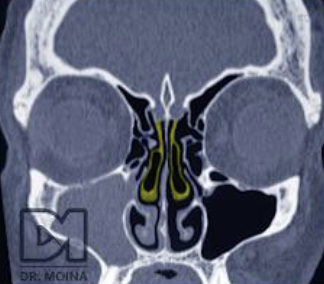

Cornete medio paradójico FP

Concha media bulosa